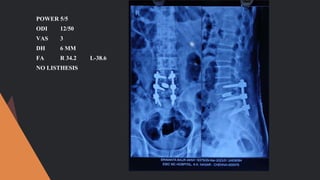

CASE -4

51/M

POWER 5/5

GRADE 1 LISTHESIS

VAS 7

ODI 24/50

DH 7

FA R 36.8 L 40.7

LLS -2.5 MM

ODI 12/50

VAS 3

DH 6 MM

FA R 34.2 L-38.6

NO LISTHESIS